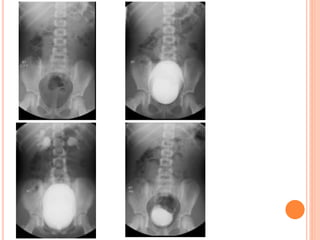

BLADDER FILLING

Early Filling

Several seconds after the contrast

material begins to flow, the minimally

filled bladder is imaged in the AP view.

A ureterocele or bladder tumor that is

well seen during early filling may

become obscured as more contrast

material enters the bladder

INTERMEDIATE FILLING

Vesicoureteral reflux can be

seen on oblique radiographs

obtained just before voiding

and can be graded after

voiding with the International

Reflux System.

PREVOIDING IMAGING

If reflux is observed during late bladder

filling, the ipsilateral renal fossa may be

imaged in the anteroposterior projection

prior to voiding.

IMAGING DURING VOIDING

Bladder capacity={Age(ys)+2}x30.

A smaller than expected voiding volume

may also indicate a neurologic abnormality

(spastic bladder) or active bladder

infection.

POSTVOIDING IMAGING

At the conclusion of voiding, each

renal fossa should be imaged. Still

images may demonstrate reflux that is

not appreciated at fluoroscopy as well

as other anomalies or abnormalities.